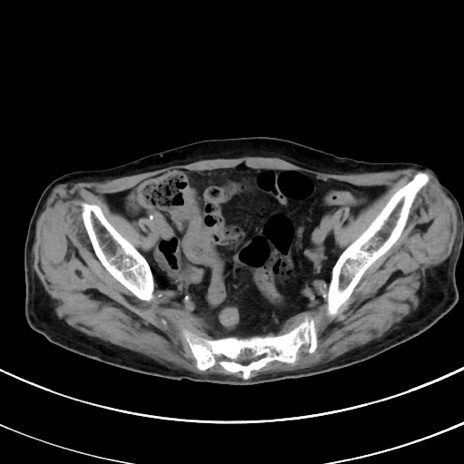

症例33(横断像)

【症例】70歳代 女性

【主訴】心窩部痛

【現病歴】延髄病変の精査・加療にて神経内科入院中。本日より心窩部痛あり。

【既往歴】虫垂炎

【身体所見】右下腹部を中心に圧痛と反跳痛あり。

【データ】WBC 10900、CRP 0.02